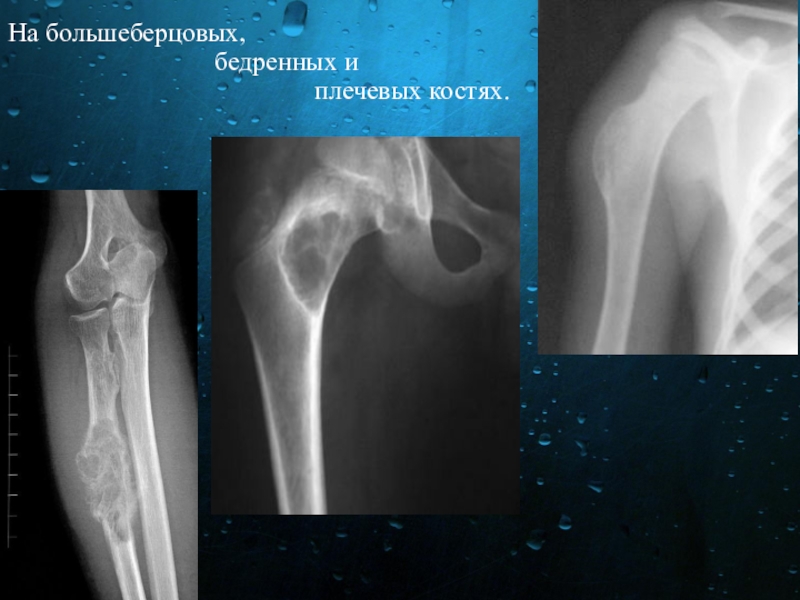

Слайд 12На большеберцовых,

бедренных и плечевых костях.

Слайд 13Поражаться также могут тела позвонков. Лечение всех видов остеом только хирургическое.

Поражаться также могут тела позвонков.   Лечение всех видов остеом только хирургическое.